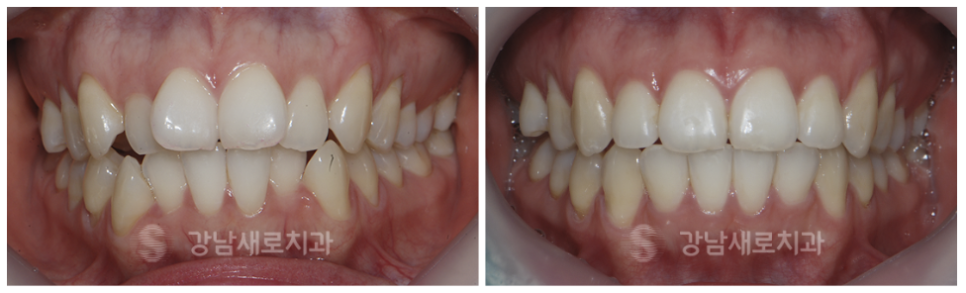

강남새로치과의 급속교정후기 는

2022.4 > 2022.10

나비 모양으로 틀어진 앞니와

전방으로 나와 있는 송곳니,

방향이 틀어져 기울어진 견치를

심미성이 우수한 위치로 이동을 시킵니다.

2021.9 > 2022.6

11번, 21번 치아인 앞니와

41번, 31번 치아인 전치만이

교정이 필요한 사례로

벌어진 앞니의 간격을 줄여

앞니의 벌어진 틈으로 빼앗기던 타인의 시선을

완벽하게 감춥니다.